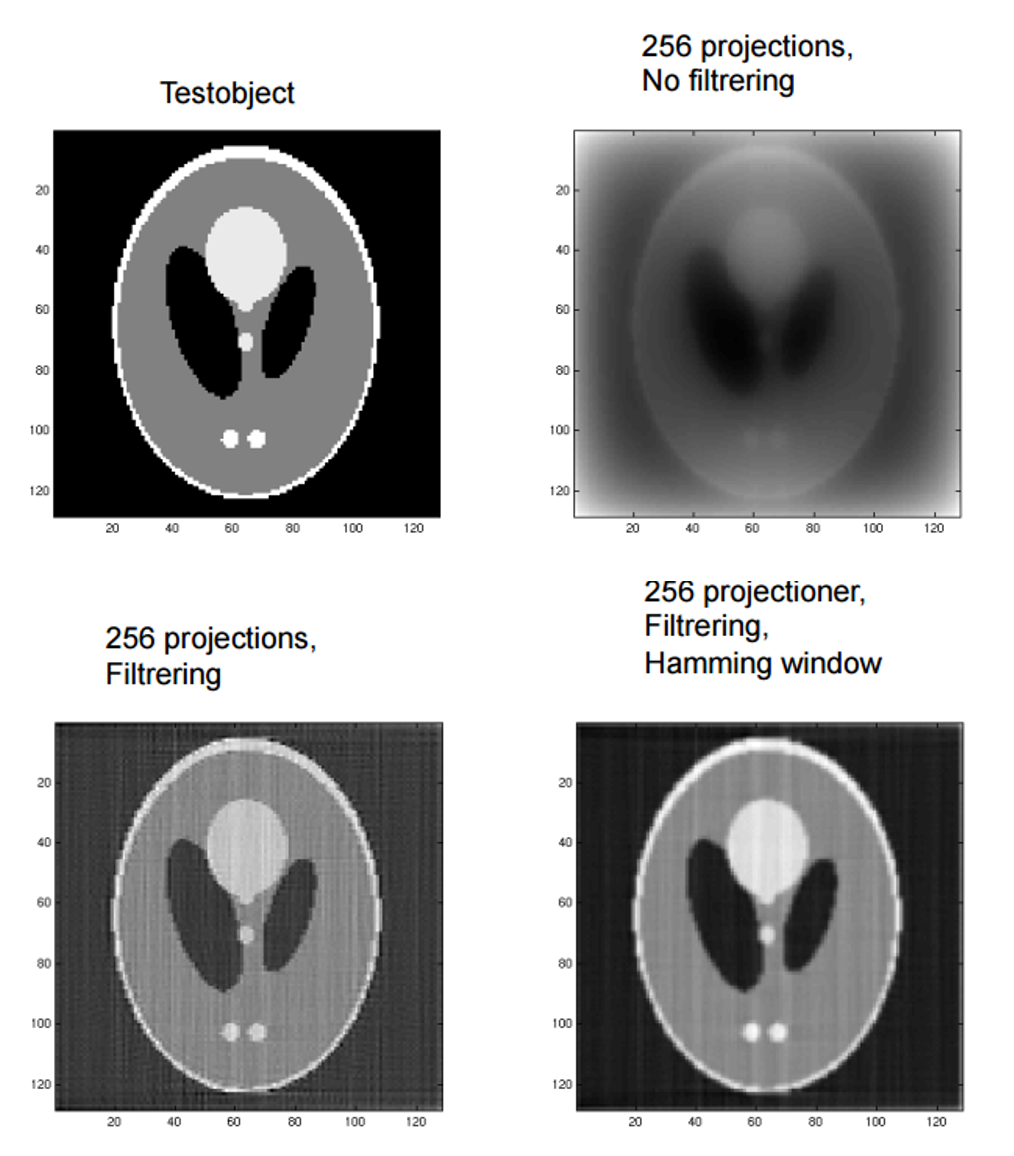

Q

What are the differences in the results between back-projection, filtered back-projection or filtered back-projection using a Hamming Window?

A

Back Projection